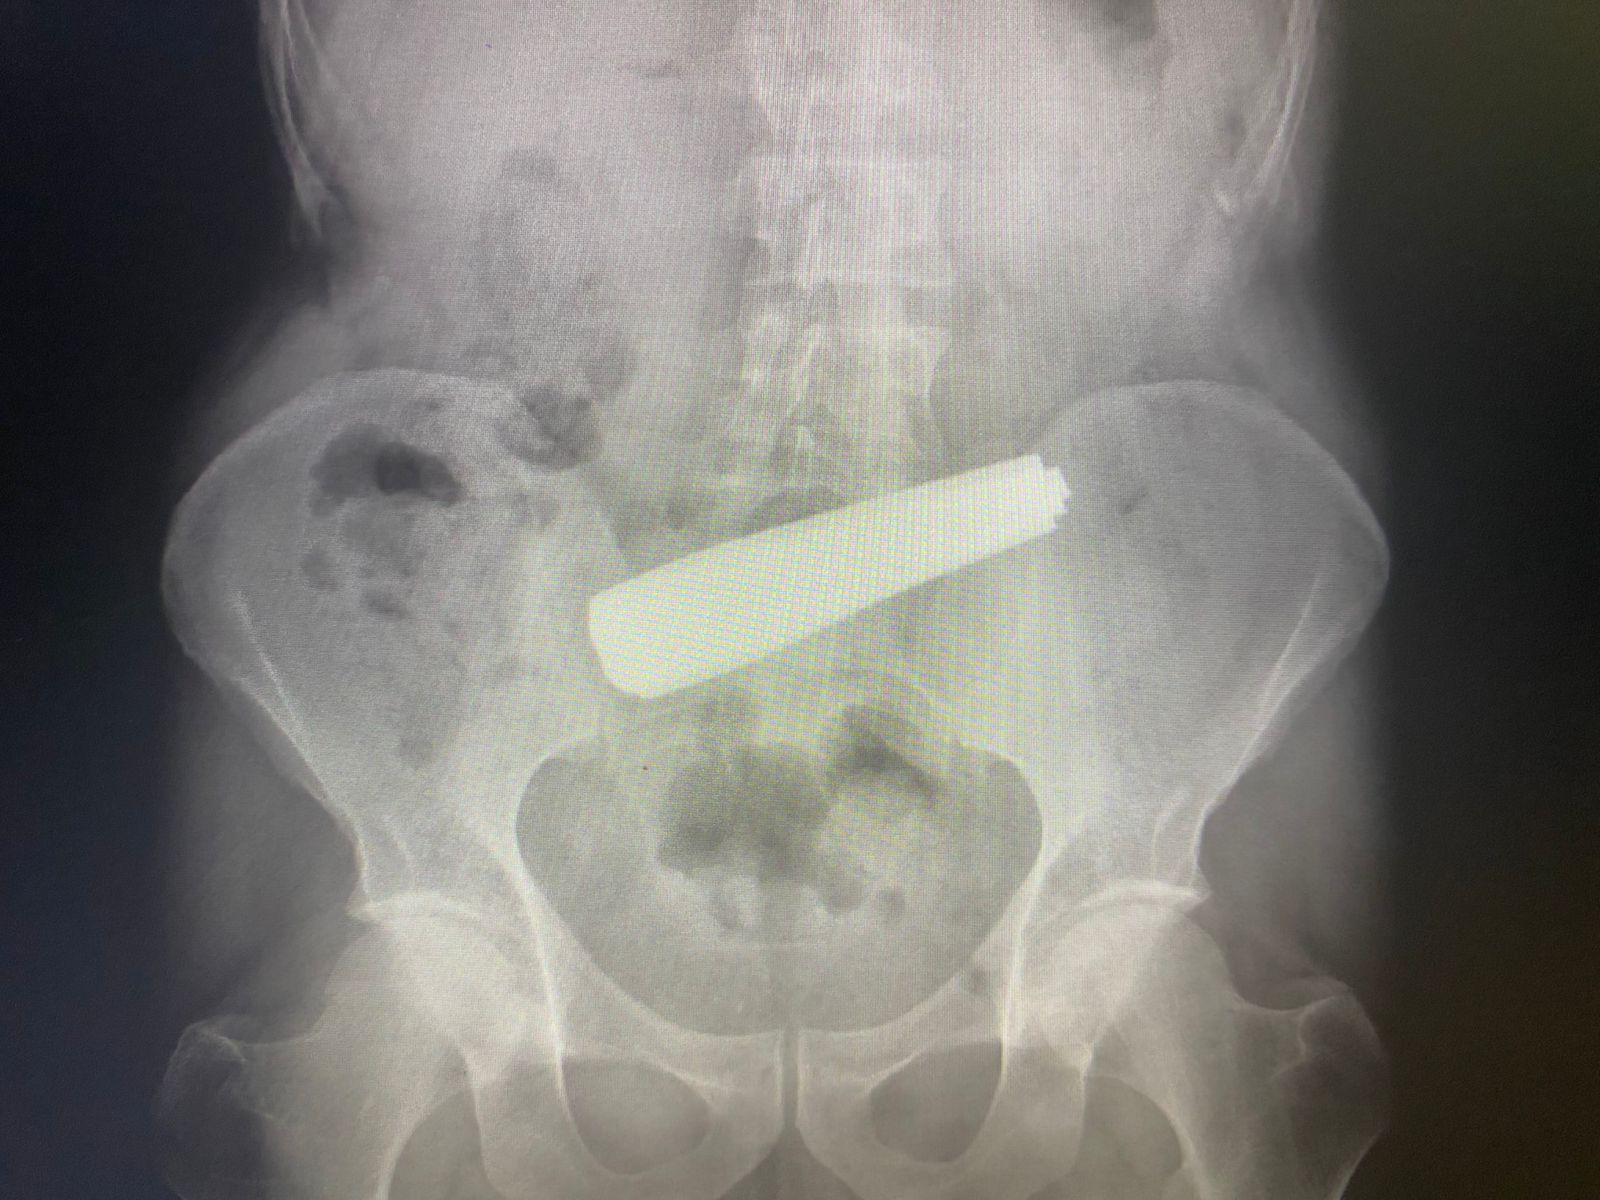

Bakıda 9 qaşıq udmuş kişinin həyatı xilas edilib.

Qeyd edək ki, 9 qaşıq udan xəstə 55 yaşlı kişidir. Pasiyentin bu hərəkətinin onun psixi vəziyyəti ilə əlaqədar olduğu ehtimal edilir.